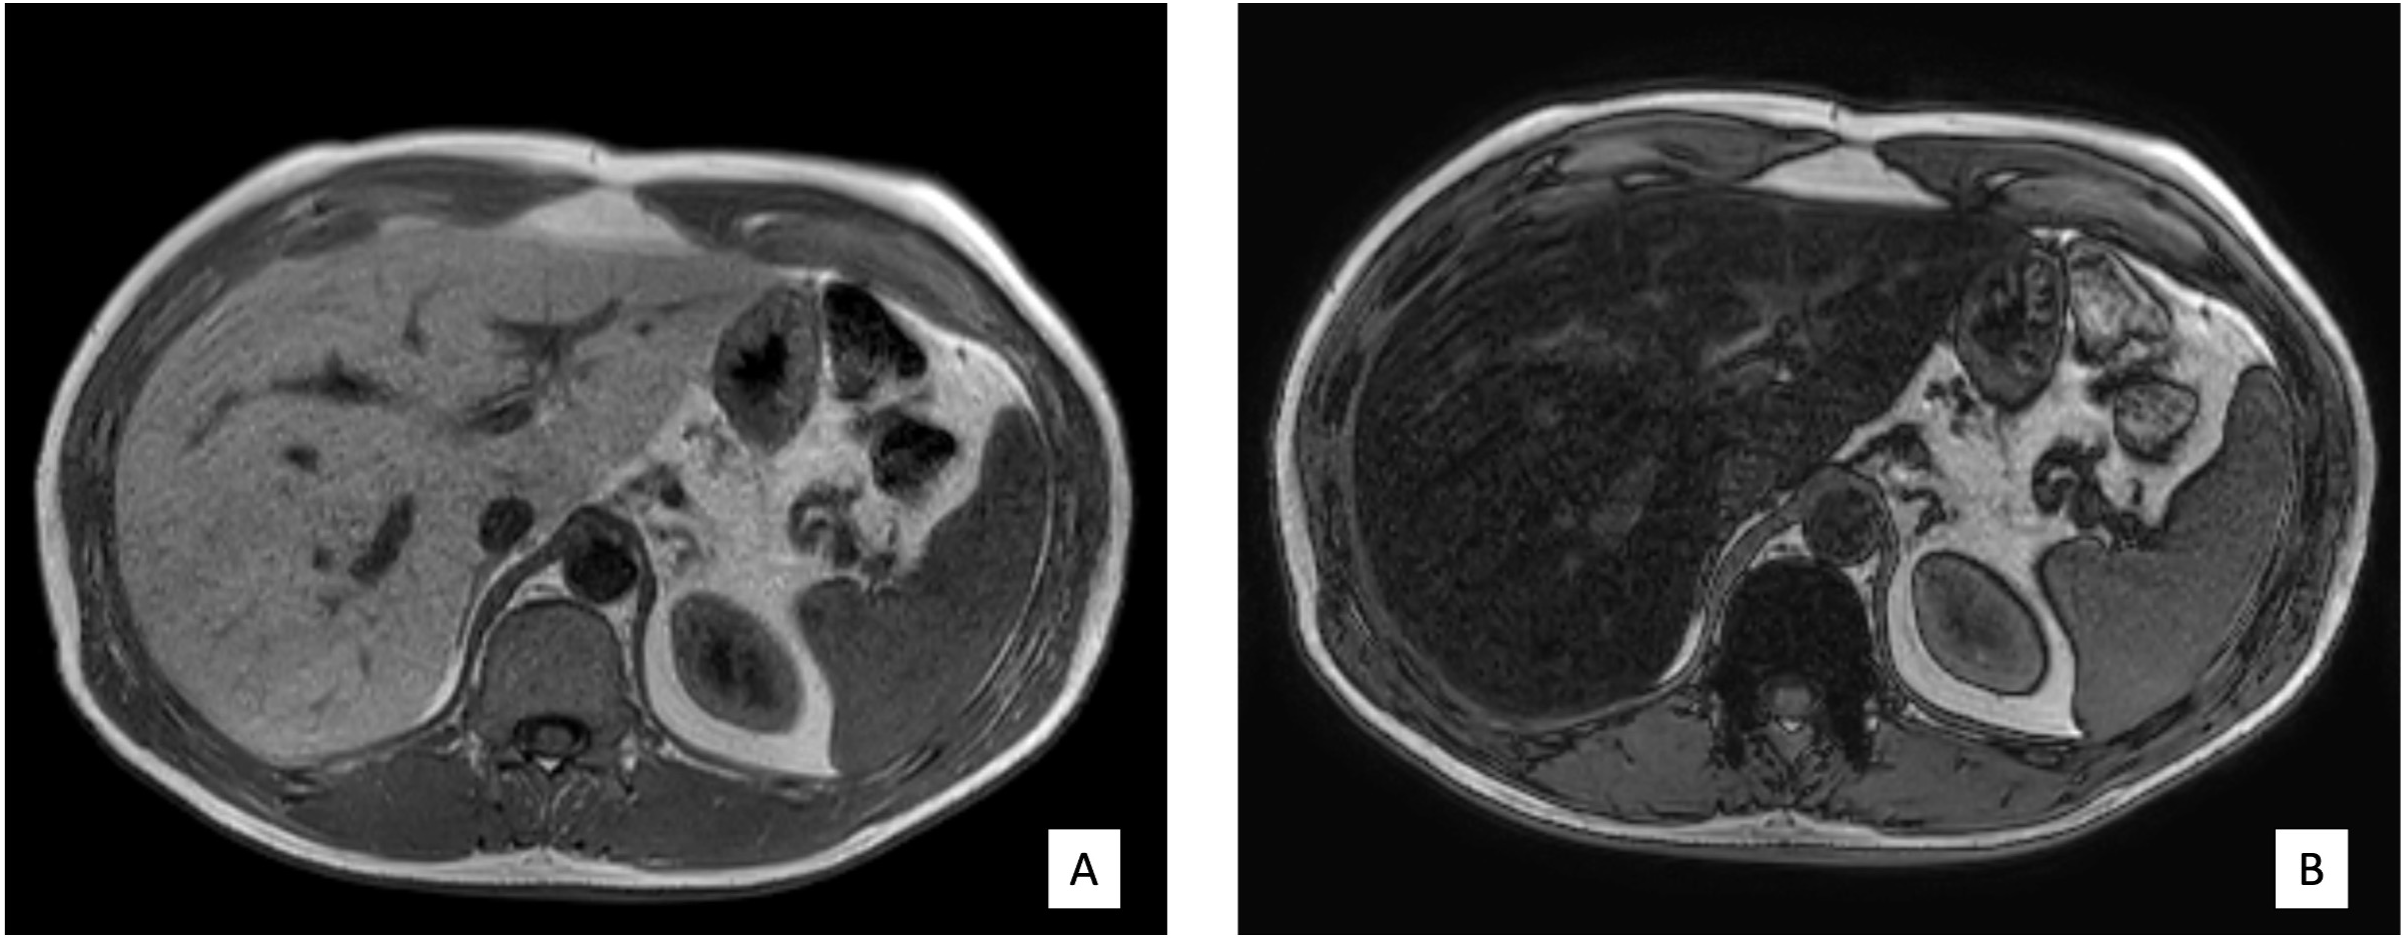

The volunteers subsequently underwent MRI: 28 subjects (23.9%) had no steatosis (steatosis percentage <5%), 64 (54.7%) had mild steatosis (steatosis percentage 6%–33%), and 25 (21.4%) had moderate steatosis (steatosis percentage 34%–66%). No subjects with severe steatosis (>66%) were identified (Table 1). GE T1-weighted in-phase images show loss of hepatic signal on opposed phase images, demonstrating the presence of steatosis (Figures 2A, B). However, a quantification of fat fraction is not possible. On the other hand, both spectroscopy and PDFF sequence allow a reliable evaluation of the liver fat fraction. The PDFF sequence allows to evaluate the whole liver (Figures 3, 4).

Figure 2

(A, B) Case 32: in-phase images showing loss of hepatic signal on opposed-phase images, demonstrating the presence of steatosis.